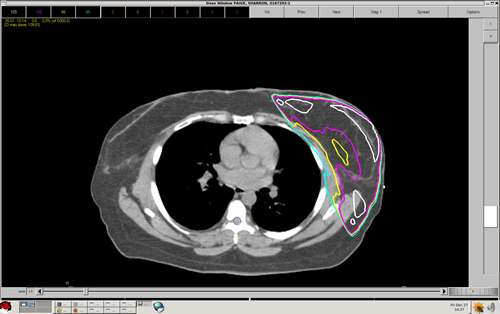

The goal of any treatment plan is to get the prescribed dose to cover the appropriate target with the least amount of collateral damage. The dose inside the target needs to be as homogeneous as possible. For this section, we will use the same basic dosimetric guideline as described earlier; no more than 5% under, and no more than 10% over. While this is the goal of our treatment planning, the patients size, shape and tumor location are all factors in your outcome.